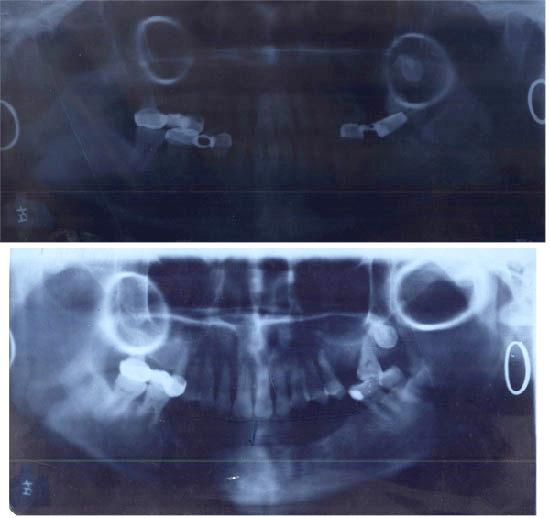

杨××,女,54岁,99年11月底因口底癌,在我院行右侧根治性颈扩清+口底癌扩大切除术+5+5的下颌骨的方块切除术+双侧颊膜瓣口底修复术。术后经过1年多的临床观察,病情稳定。患者要求义齿修复,因其下颌骨前部缺失,已低于唇,舌侧软组织,所以修复很困难,需增加牙槽嵴高度。2000年11月8日全麻下行垂直牵引器植入术。经过术后7天间歇期,于11月14日每天1次牵引升高移动骨段,于11月3日牵引结束,共升高12MM,已达到术前设计要求,经过8周的稳定期后,经X线片检查见骨间隙内新能生成良好,移动骨段稳定,牙槽明显恢复。经过半个月的软组织恢复。于3月末给预铸造活动义齿修复,其面型及咀嚼功能均得到了比较理想的恢复。